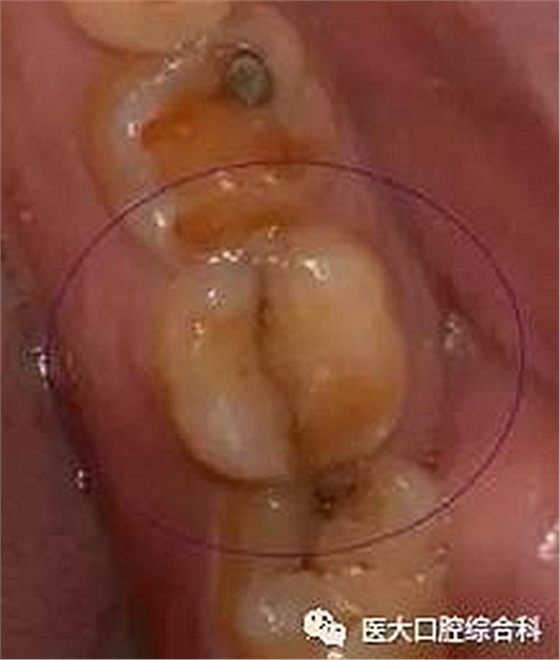

牙隱裂(cracked tooth)又稱不全牙裂或牙微裂。指牙冠表面非生理性細小裂紋,常不易被發(fā)現(xiàn)。牙隱裂的裂紋常滲入到牙本質結構,是臨床上常見的引起牙痛的原因之一。

隱裂的位置多比較隱匿,常與天然窩溝的位置重疊,并向一側或兩側邊緣嵴延伸。

一般出現(xiàn)上述臨床表現(xiàn)但未查及明顯的牙體、牙周損害時,??漆t(yī)生可借助顯微鏡、染色等特殊方法,對疑似隱裂的牙齒進行進一步檢查。此外,有時將探針置于裂隙處加壓或用力撬動,或將棉簽置于可疑牙的牙尖上,使患者進行咬診,可出現(xiàn)撕裂樣疼痛,則可進一步診斷。